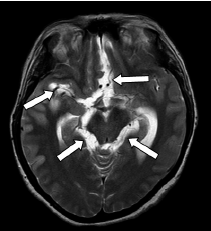

Figura 1 Resonancia magnética cerebral, corte axial potenciado en T2, en la cual se observan múltiples dilataciones en las cisternas de la base, de la lámina terminal y la silviana derecha, debidas a quistes de cisticercosis racemosa (sic) (flechas).

Según los hallazgos en las imágenes de resonancia magnética cerebral, los casos informados se clasificaron como neurocisticercosis extraparenquimatosa con quistes racimosos en el espacio subaracnoideo asociados a la intensa reacción inflamatoria (figura 1), (figura 4).

En los dos casos que se presentan, la neurocisticercosis racemosa (sic) se acompañó de hidrocefalia y aracnoiditis; en el primer caso, además, se detectó vasculitis de la arteria cerebral media derecha en sus porciones proximales adyacentes a las cisternas de la base y la silviana derecha, relacionada con la presencia de cisticercos (figura 1). En el segundo caso, se detectó dilatación y obstrucción del cuarto ventrículo por aracnoiditis (figura 3), hallazgo que explica la causa del vómito incoercible, debido a su estrecha relación anatómica con el área postrema (control del vómito).